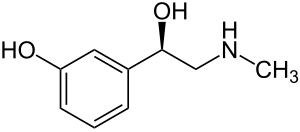

| Formula | C9H13NO2 |

| Molar mass | 167.205 g·mol−1 |

SMILES

InChI

Phenylephrine is a medication primarily used as a decongestant, to dilate the pupil, to increase blood pressure, and to relieve hemorrhoids.[2][3] While marketed as a decongestant, taken by mouth at recommended doses it is of unclear benefit for hay fever.[2][5] It can be taken by mouth, given by injection into a vein or muscle, or applied to the skin.[2]

Common side effects when taken by mouth or injected include nausea, headache, and anxiety.[2] Use on hemorrhoids is generally well tolerated.[2] Severe side effects may include a slow heart rate, intestinal ischemia, chest pain, kidney failure, and tissue death at the site of injection.[2][3] It is unclear if use during pregnancy or breastfeeding is safe.[2] Phenylephrine is a selective α1-adrenergic receptor activator which results in the constriction of both arteries and veins.[2]

Phenylephrine is a sympathomimetic drug, which means that it mimics the actions of epinephrine (commonly known as adrenaline) or norepinephrine. Phenylephrine selectively binds to alpha-1 receptors which cause blood vessels to constrict.[21]

Whereas pseudoephedrine causes both vasoconstriction and increase of mucociliary clearance through its nonspecific adrenergic activity, phenylephrine's selective α-adrenergic agonism causes vasoconstriction alone, creating a difference in their methods of action.